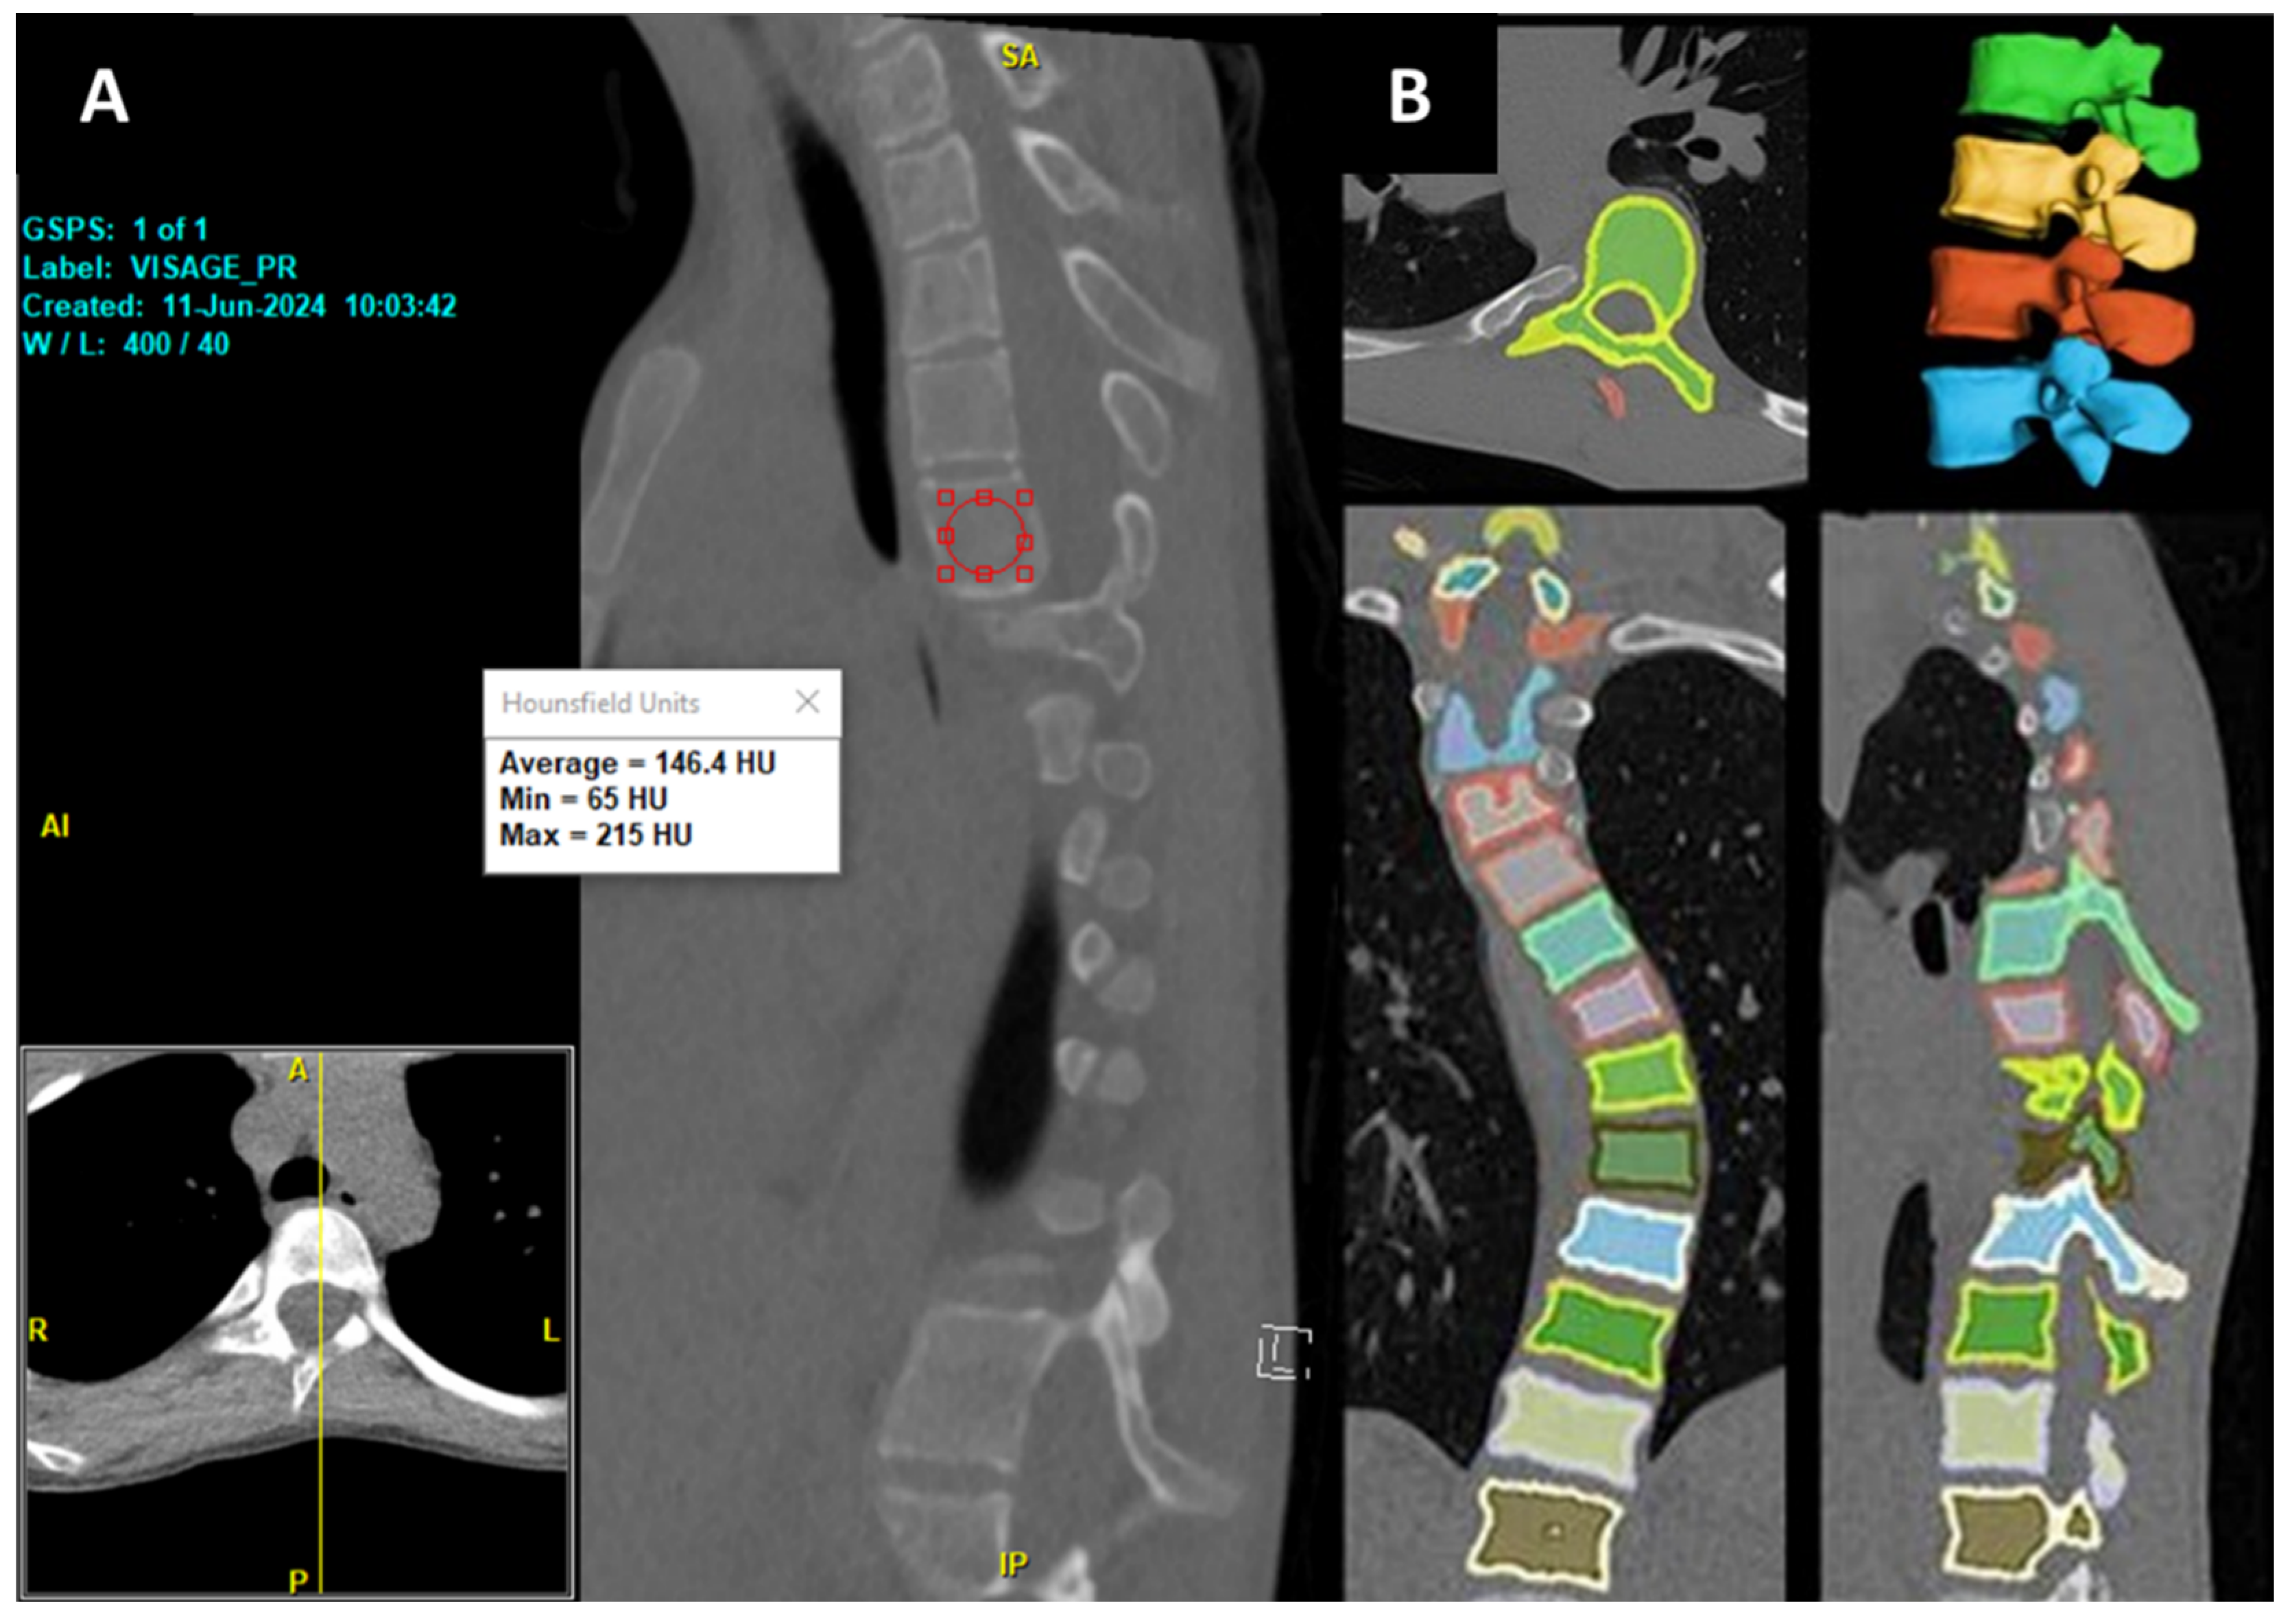

32]. Recently, a new DR-based model has been developed by researchers at Cornell to automate the volumetric assessment of Hounsfield Units (HU), trained on a combination of publicly available CT datasets and deidentified institutional lumbar CT scans, and our team has internally validated the model against DXA (Dual-energy X-ray Absorptiometry) metrics [

33]. The volumetric HU correlated most strongly with DXA bone mineral density (BMD) at L2 (Spearman ρ = 0.75,

p < 0.0001). The model was able to efficiently segment each vertebra and quantify both the volume and volumetric HU of the whole imaging studies from all available kernels in about 30 s per CT scan.

In addition to the DXA, we found that the same DR model also correlated strongly with surgeons’ intraoperative assessment of the operated vertebrae [

34]. Additionally, it has also been able to assess the volume and volumetric HU for neurofibromatosis type 1 patients who underwent spine surgery, showing significantly lower bone density than normal controls [

35]. This provides a faster, more objective, and comprehensive alternative to traditional manual methods. This is especially true since the conventional mid-sagittal method of opportunistic HU measurement is confounded by a constant shift in the sagittal plane due to the scoliotic condition of the vertebrae (

Figure 9), as well as variability in HU values at the vertebral bodies. However, these findings are based on small, single-center cohorts, limiting generalizability. Validation in larger, multicenter cohorts is essential to confirm the model’s reliability, accuracy, and clinical utility for preoperative planning and spinal bone health monitoring, particularly in diverse scoliotic populations.